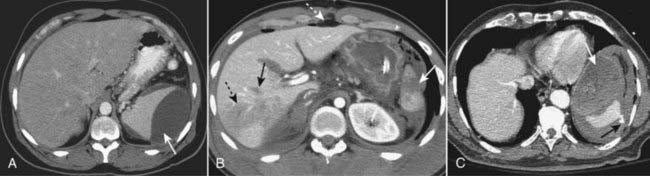

image

Figure 17-7 Hepatic trauma, three different patients.

A, There is a lenticular fluid collection involving the lateral portion of the right lobe of the liver that represents a subcapsular hematoma (solid black arrow). A laceration of the right lobe is also present (dotted black arrow). B, There are multiple lacerations of the right lobe of the liver (black circle). C, Active extravasation of contrast-enhanced blood (solid black arrow) is seen from a large intrahepatic laceration with hematoma (dotted black arrow) and there is both subcapsular blood and hemoperitoneum (solid white arrow).